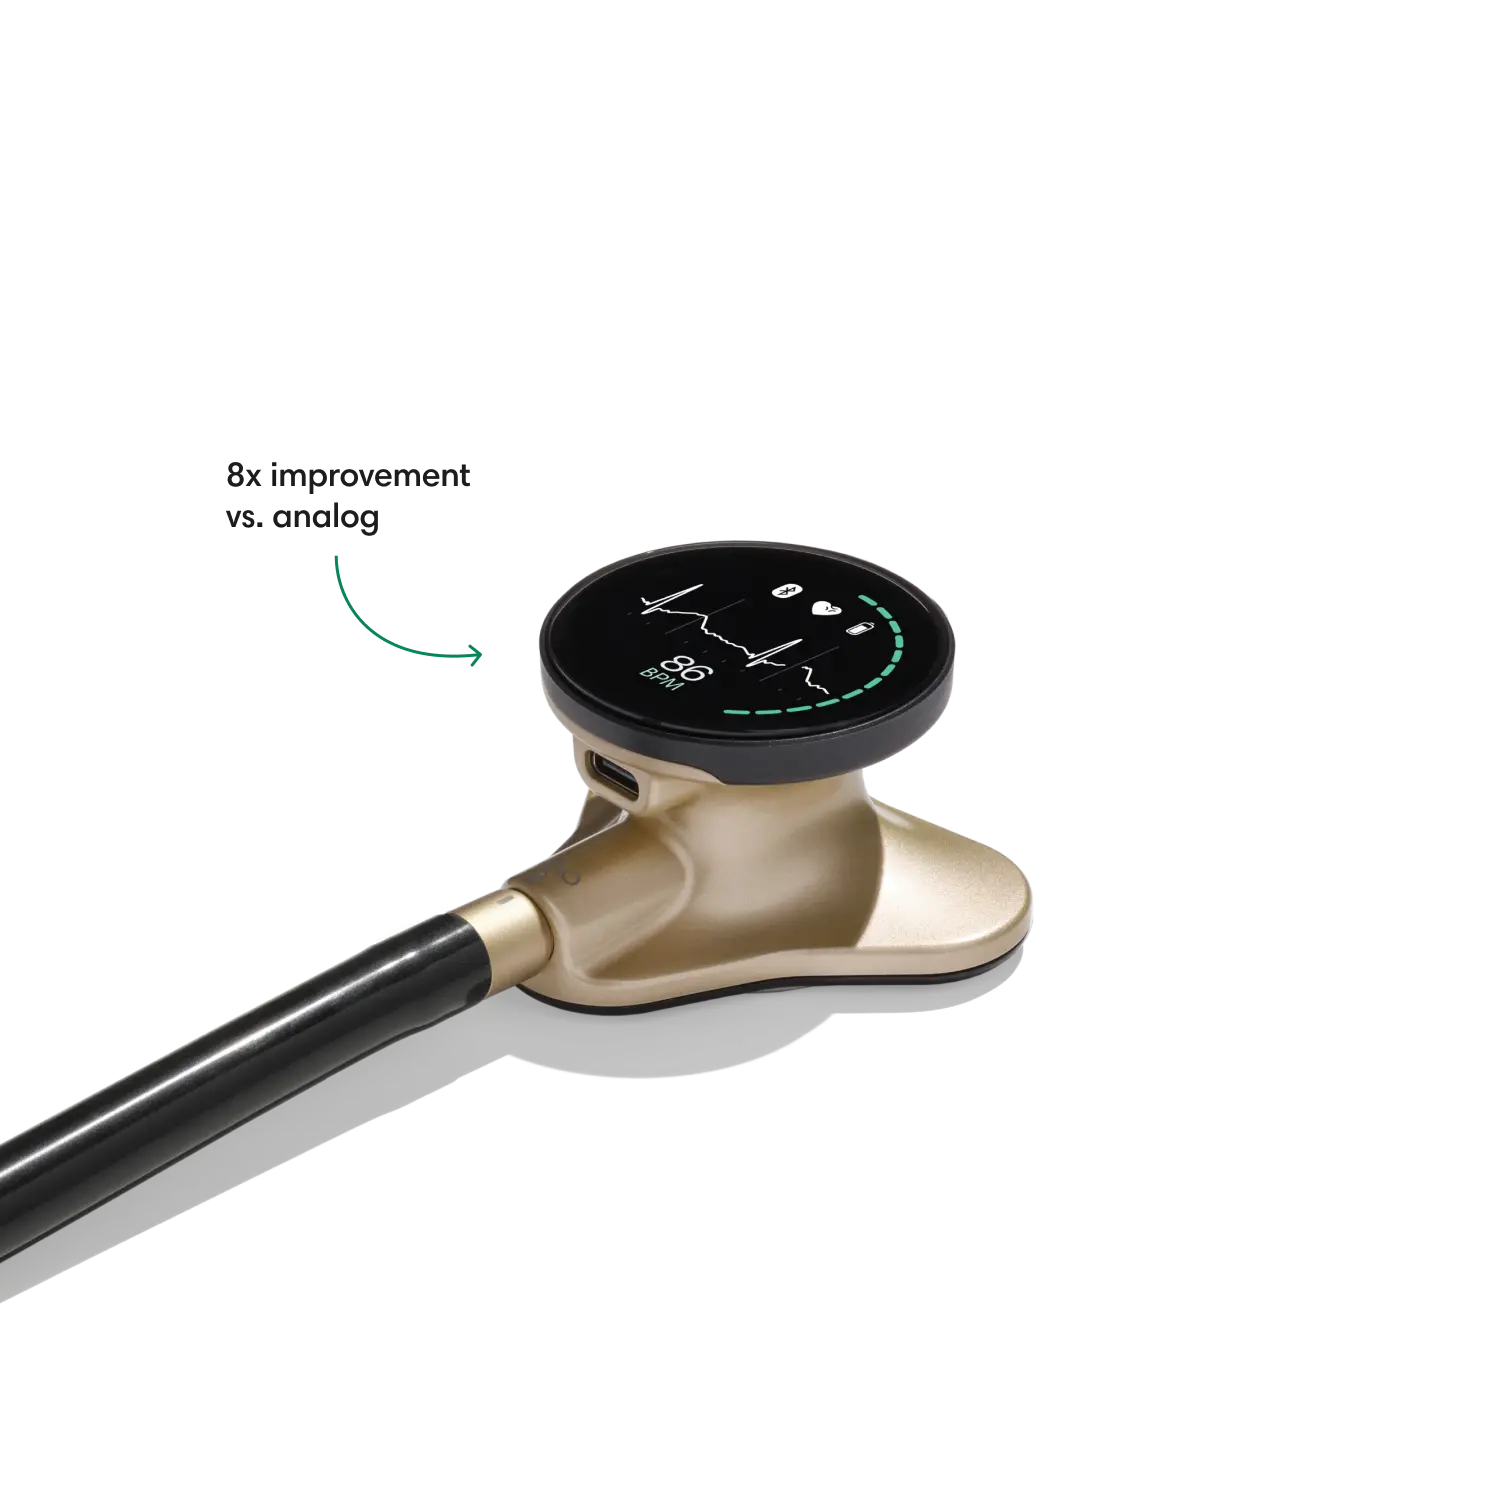

Instead of using a hollow tube like with an analog stethoscope, heart and lung sounds are delivered digitally through ear tip speakers. This results in unparalleled audio quality and sound cancellation.

Go beyond sound alone.

For the first time ever, measure heart rate, visualize 3-lead ECG, and see detection results — right on a built-in, full-color display.

- Reduces background noise 8x better vs. a typical analog stethoscope.